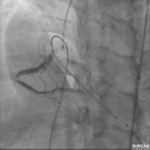

A 76-year-old woman presented with angina like chest pain and dyspnea on exertion. Stress MPI showed lateral ischemia. Medical history : HTN, HLD, Gout Medications: Aspirin, Amlodipine, Metoprolol XL, Losartan,…